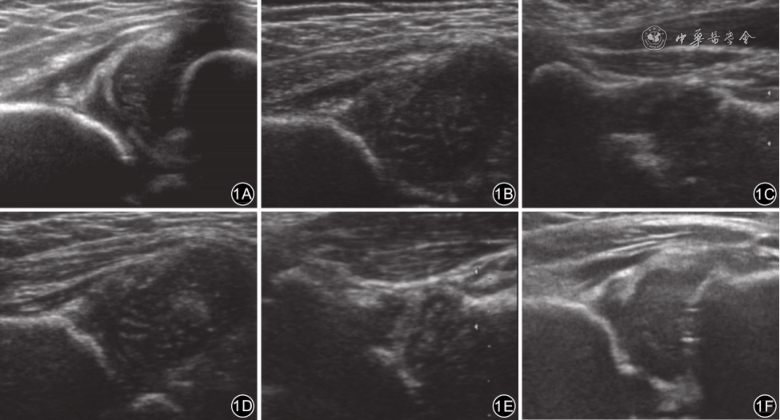

66例68髋吊带佩戴时间为2~22(10.2±4.0)周,成功50例51髋、失败16例17髋,成功率75.0%(51/68)。成功的51髋中,Ⅱa(-)型2髋、Ⅱb型21髋、Ⅱc型17髋、D型6髋、Ⅲ型4髋和Ⅳ型1髋。失败的17髋中,10髋为Graf Ⅱb或IHDI Ⅱ型,更换为外展支具继续治疗随访中;5髋为Graf Ⅱc型1髋、D型1髋、Ⅳ型3髋,行闭合复位石膏固定;2髋为Graf Ⅳ型,行切开复位石膏固定。66例DDH患儿治疗期间无股骨头缺血性坏死及股神经麻痹发生。典型病例见图1。